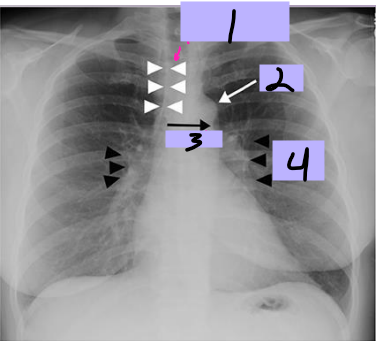

Paratracheal stripe

#1

Aortic knob

#2

AP window

#3

Hila

#4